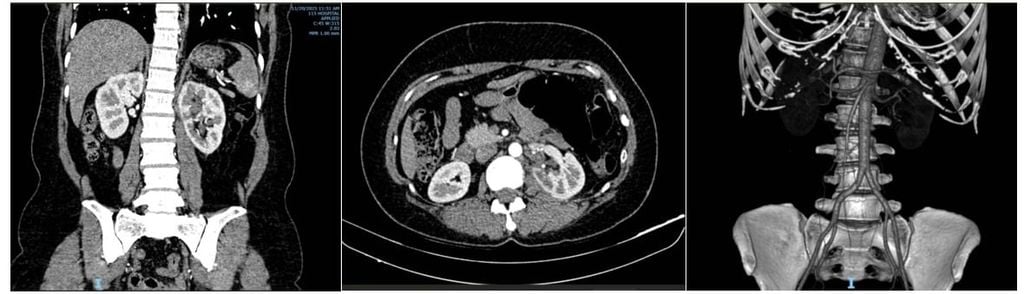

Người bệnh tái khám sau 1 tháng hoàn toàn khỏe mạnh, không đau, 3 lỗ đặt Trocar nội soi lành sẹo, chụp CT-Scan có tiêm thuốc cản quang không còn hình ảnh túi phình rò động tĩnh mạch, xét nghiệm chức năng thận bình thường.

Hình 3. Hình CT-Scan sau 1 tháng (dựng hình mạch máu thận không còn túi phình động mạch)